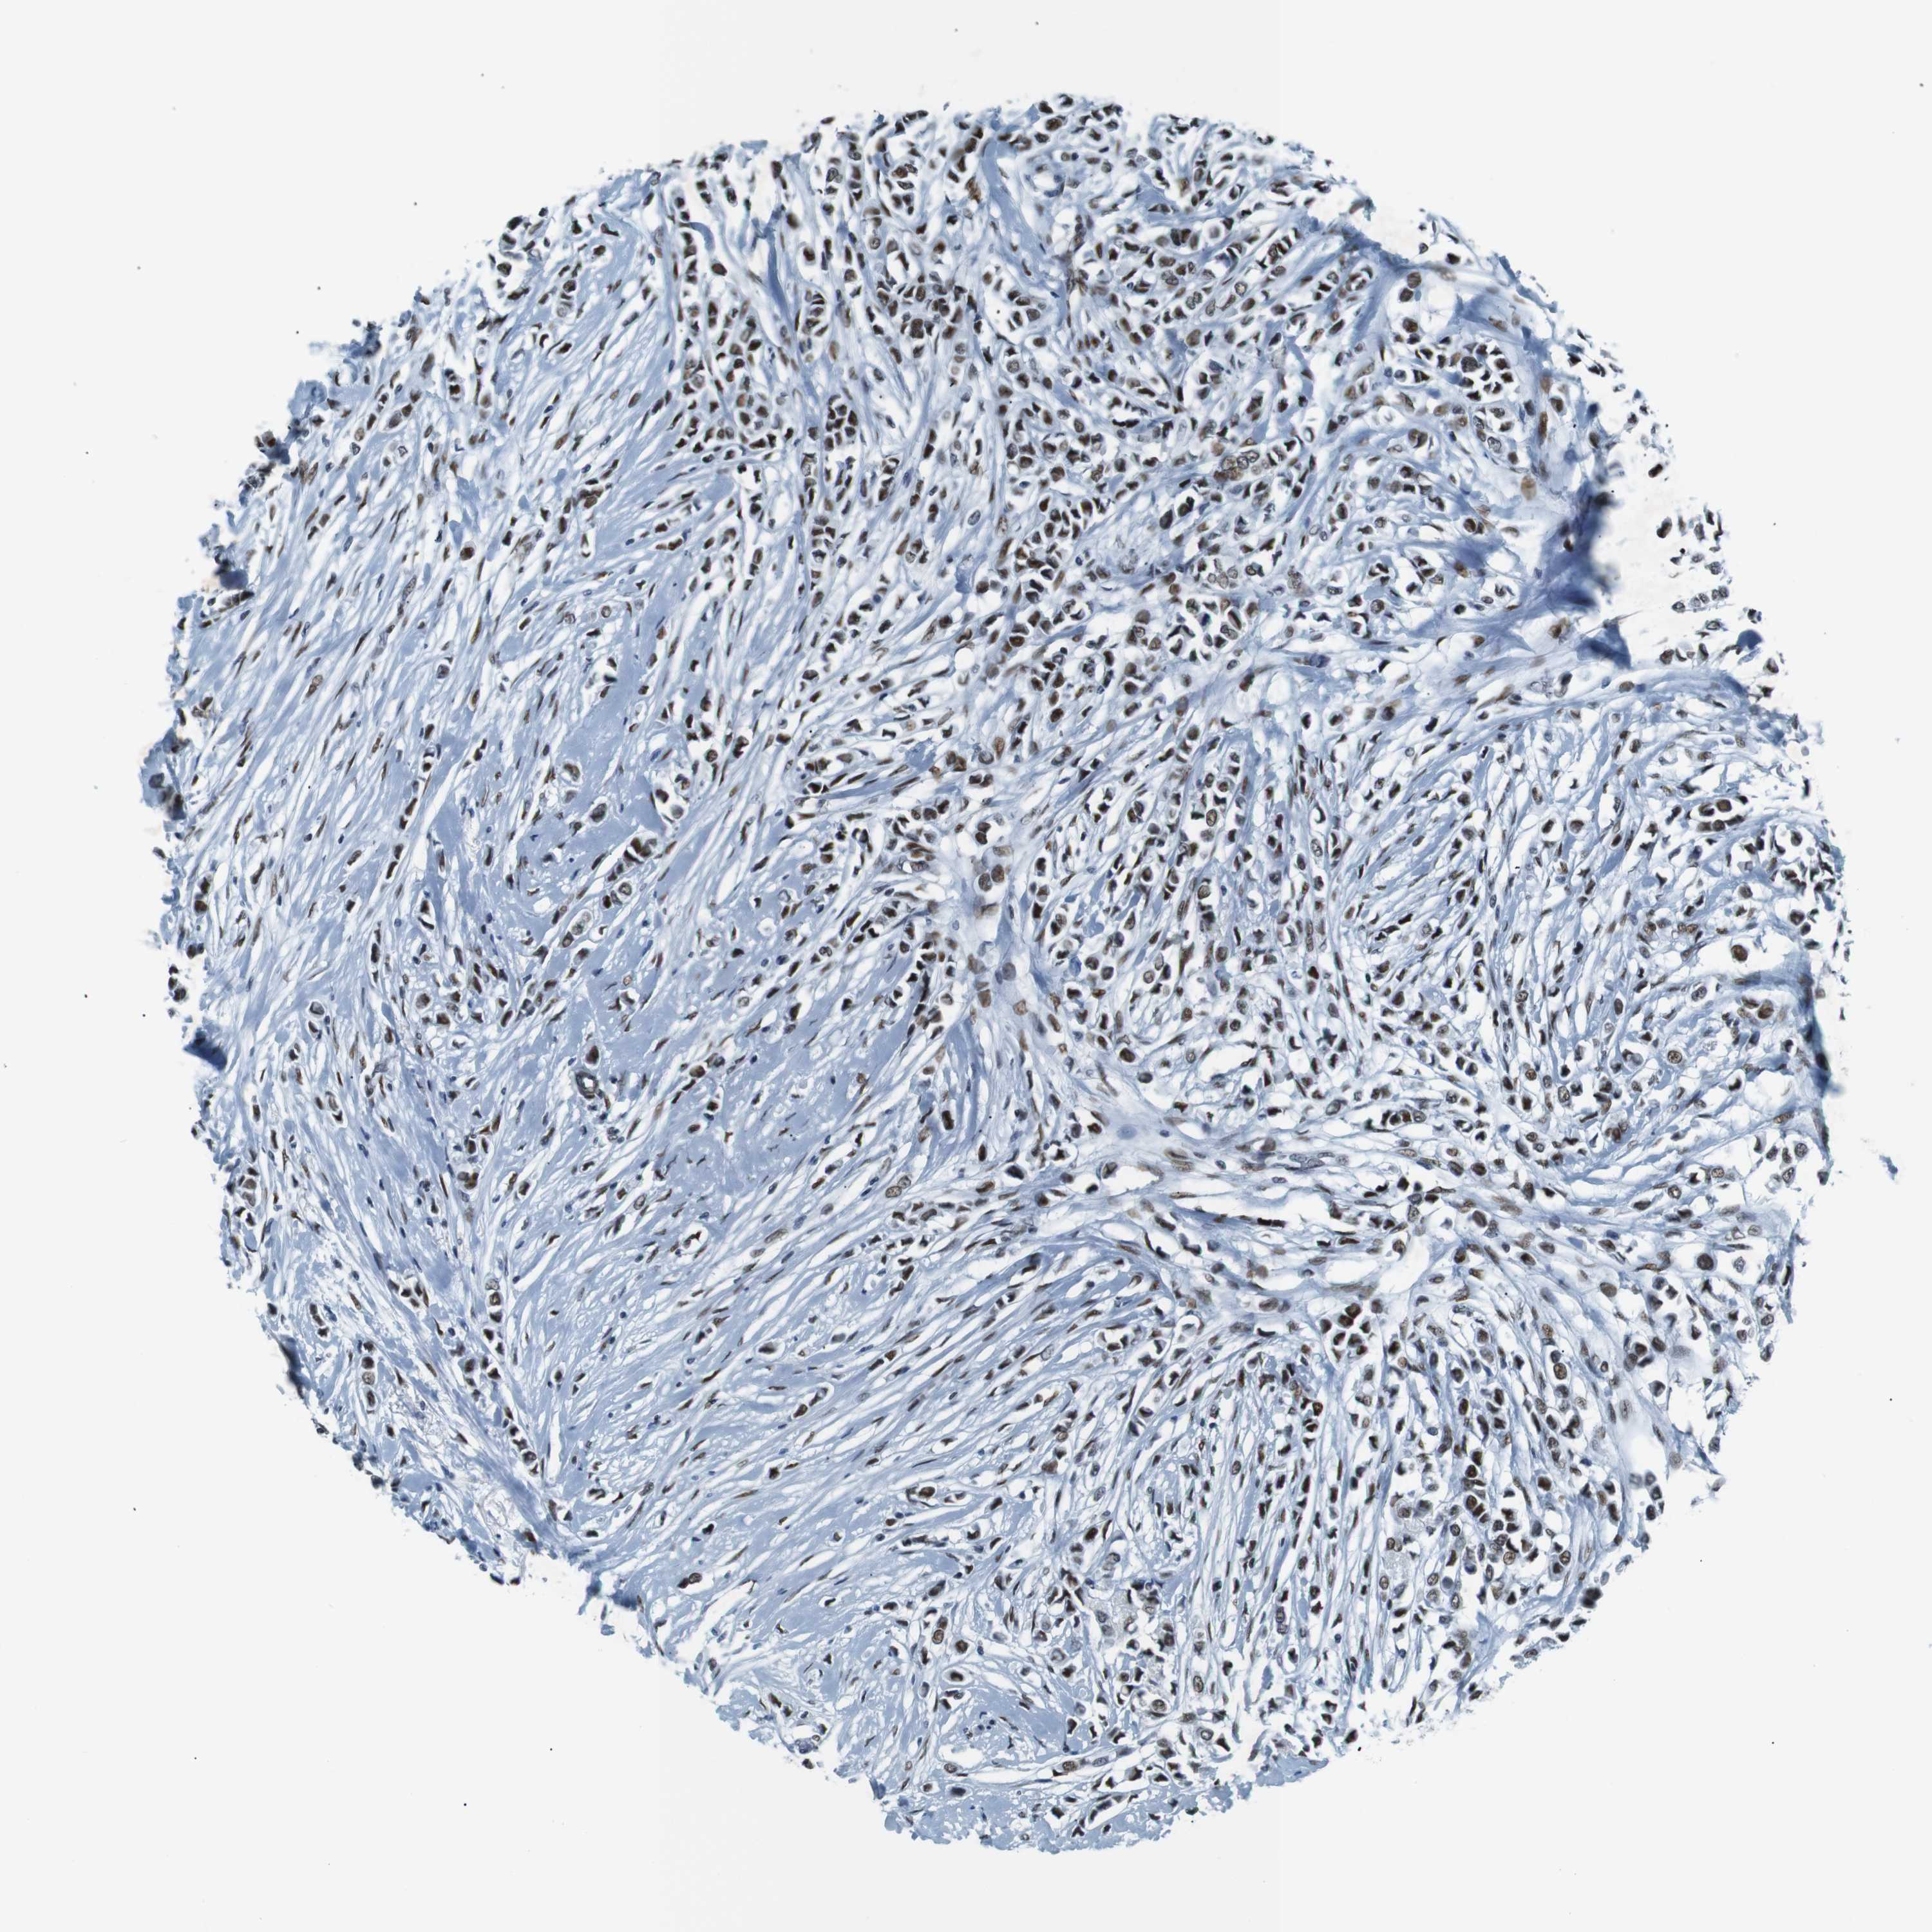

CANCER BREAST CANCER Show tissue menu

BRCA TCGA BRCA VALIDATION PROTEIN EXPRESSION